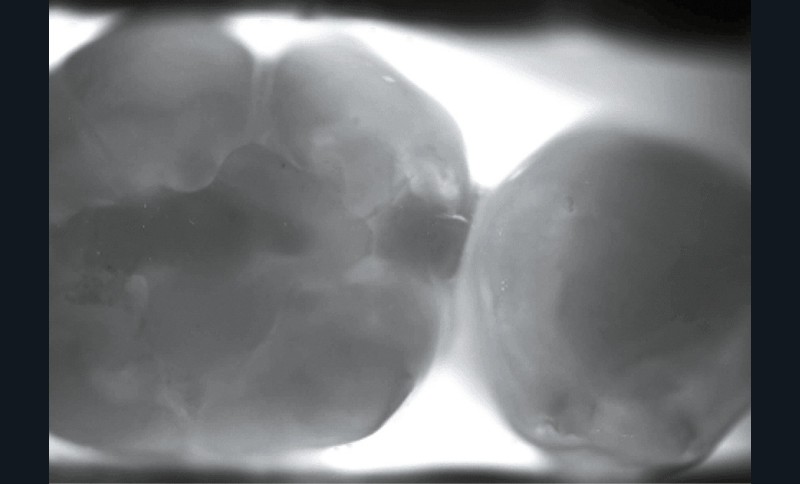

Planmeca, avec Emerald S, permet, avec un embout dédié, une détection par transillumination (fig. 2a et 2b).

Détection de carie par transillumination

Le principe repose sur l’envoi d’un faisceau lumineux infrarouge sur la dent.

L’émail d’une dent étant transparent, la lumière ne sera stoppée que dans les zones rendues opaques par le changement de structure minérale de cet émail : la carie (fig. 4).